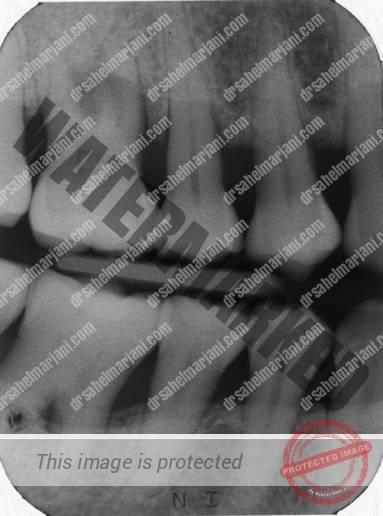

انواع مختلف تصاویر رادیوگرافی به توسعه طرح های درمان پریودنتال کمک می کنند. این “بازده درمانی” را می توان با تصاویر رادیوگرافی پانورامیک دهانی بدست آورد که با نماهای انتخابی داخل دهانی تکمیل می شوند. به نظر می رسد تصاویر رادیوگرافی پانورامیک دیجیتال دهانی که روی صفحه نمایش مشاهده می شوند، نسبت به پرینت ها یا فیلم ها مزایایی دارند. روش های جدیدتر تصویربرداری، مانند توموگرافی کامپیوتری با پرتو مخروطی (حجم دیجیتال)، ممکن است مزایایی از خود نشان دهند، اما تجربه نشان داده است که احتمالاً تصاویر رادیوگرافی ردیابی دیجیتالی یک ابزار تحقیقاتی بدون کاربرد بالینی زیاد خواهد بود.

در بررسی های انجام شده با هدف پوشش دادن اطلاعات تشخیصی مهم پریودنتال قابل دستیابی از تصاویر رادیوگرافی معمولی و در نظر گرفتن اینکه چگونه، با توجه به درمان پریودنتال، رادیوگرافی ممکن است بر مدیریت بیماری تأثیر بگذارد نشان دادند که ویژگی های مختلف علائم تشخیصی پریودنتال در تصاویر رادیوگرافی آشکار هستند، که تجسم آنها ممکن است به نمای رادیوگرافی انتخاب شده بستگی داشته باشد، که بین چسبندگی بالینی و ارتفاع استخوان رادیوگرافی رابطه وجود دارد، و اینکه رادیوگرافی ها می توانند در تمام مراحل استفاده شوند.

بسیاری از ویژگی های مهم بالینی بیماری های پریودنتال در رادیوگرافی مشهود نیست (جدول ۲)، اما با این وجود، بررسی رادیوگرافی تنها پس از معاینه و ثبت دقیق بالینی ضروری است. در صورت مشاهده علائم بالینی پریودنتیت، کاوش عمق پاکت و/یا فرورفتگی، که در معاینه بالینی مشاهده می شود، معاینه رادیوگرافی اطلاعاتی را در مورد موارد زیر به دست می دهد: الگوهای آشکار از دست دادن استخوان، یکنواخت یا زاویه ای. طول ریشه دندان، مورفولوژی و توپوگرافی؛ و مهمتر از همه طول ریشه دندان از نظر رادیوگرافی توسط استخوان آلوئول احاطه شده است.